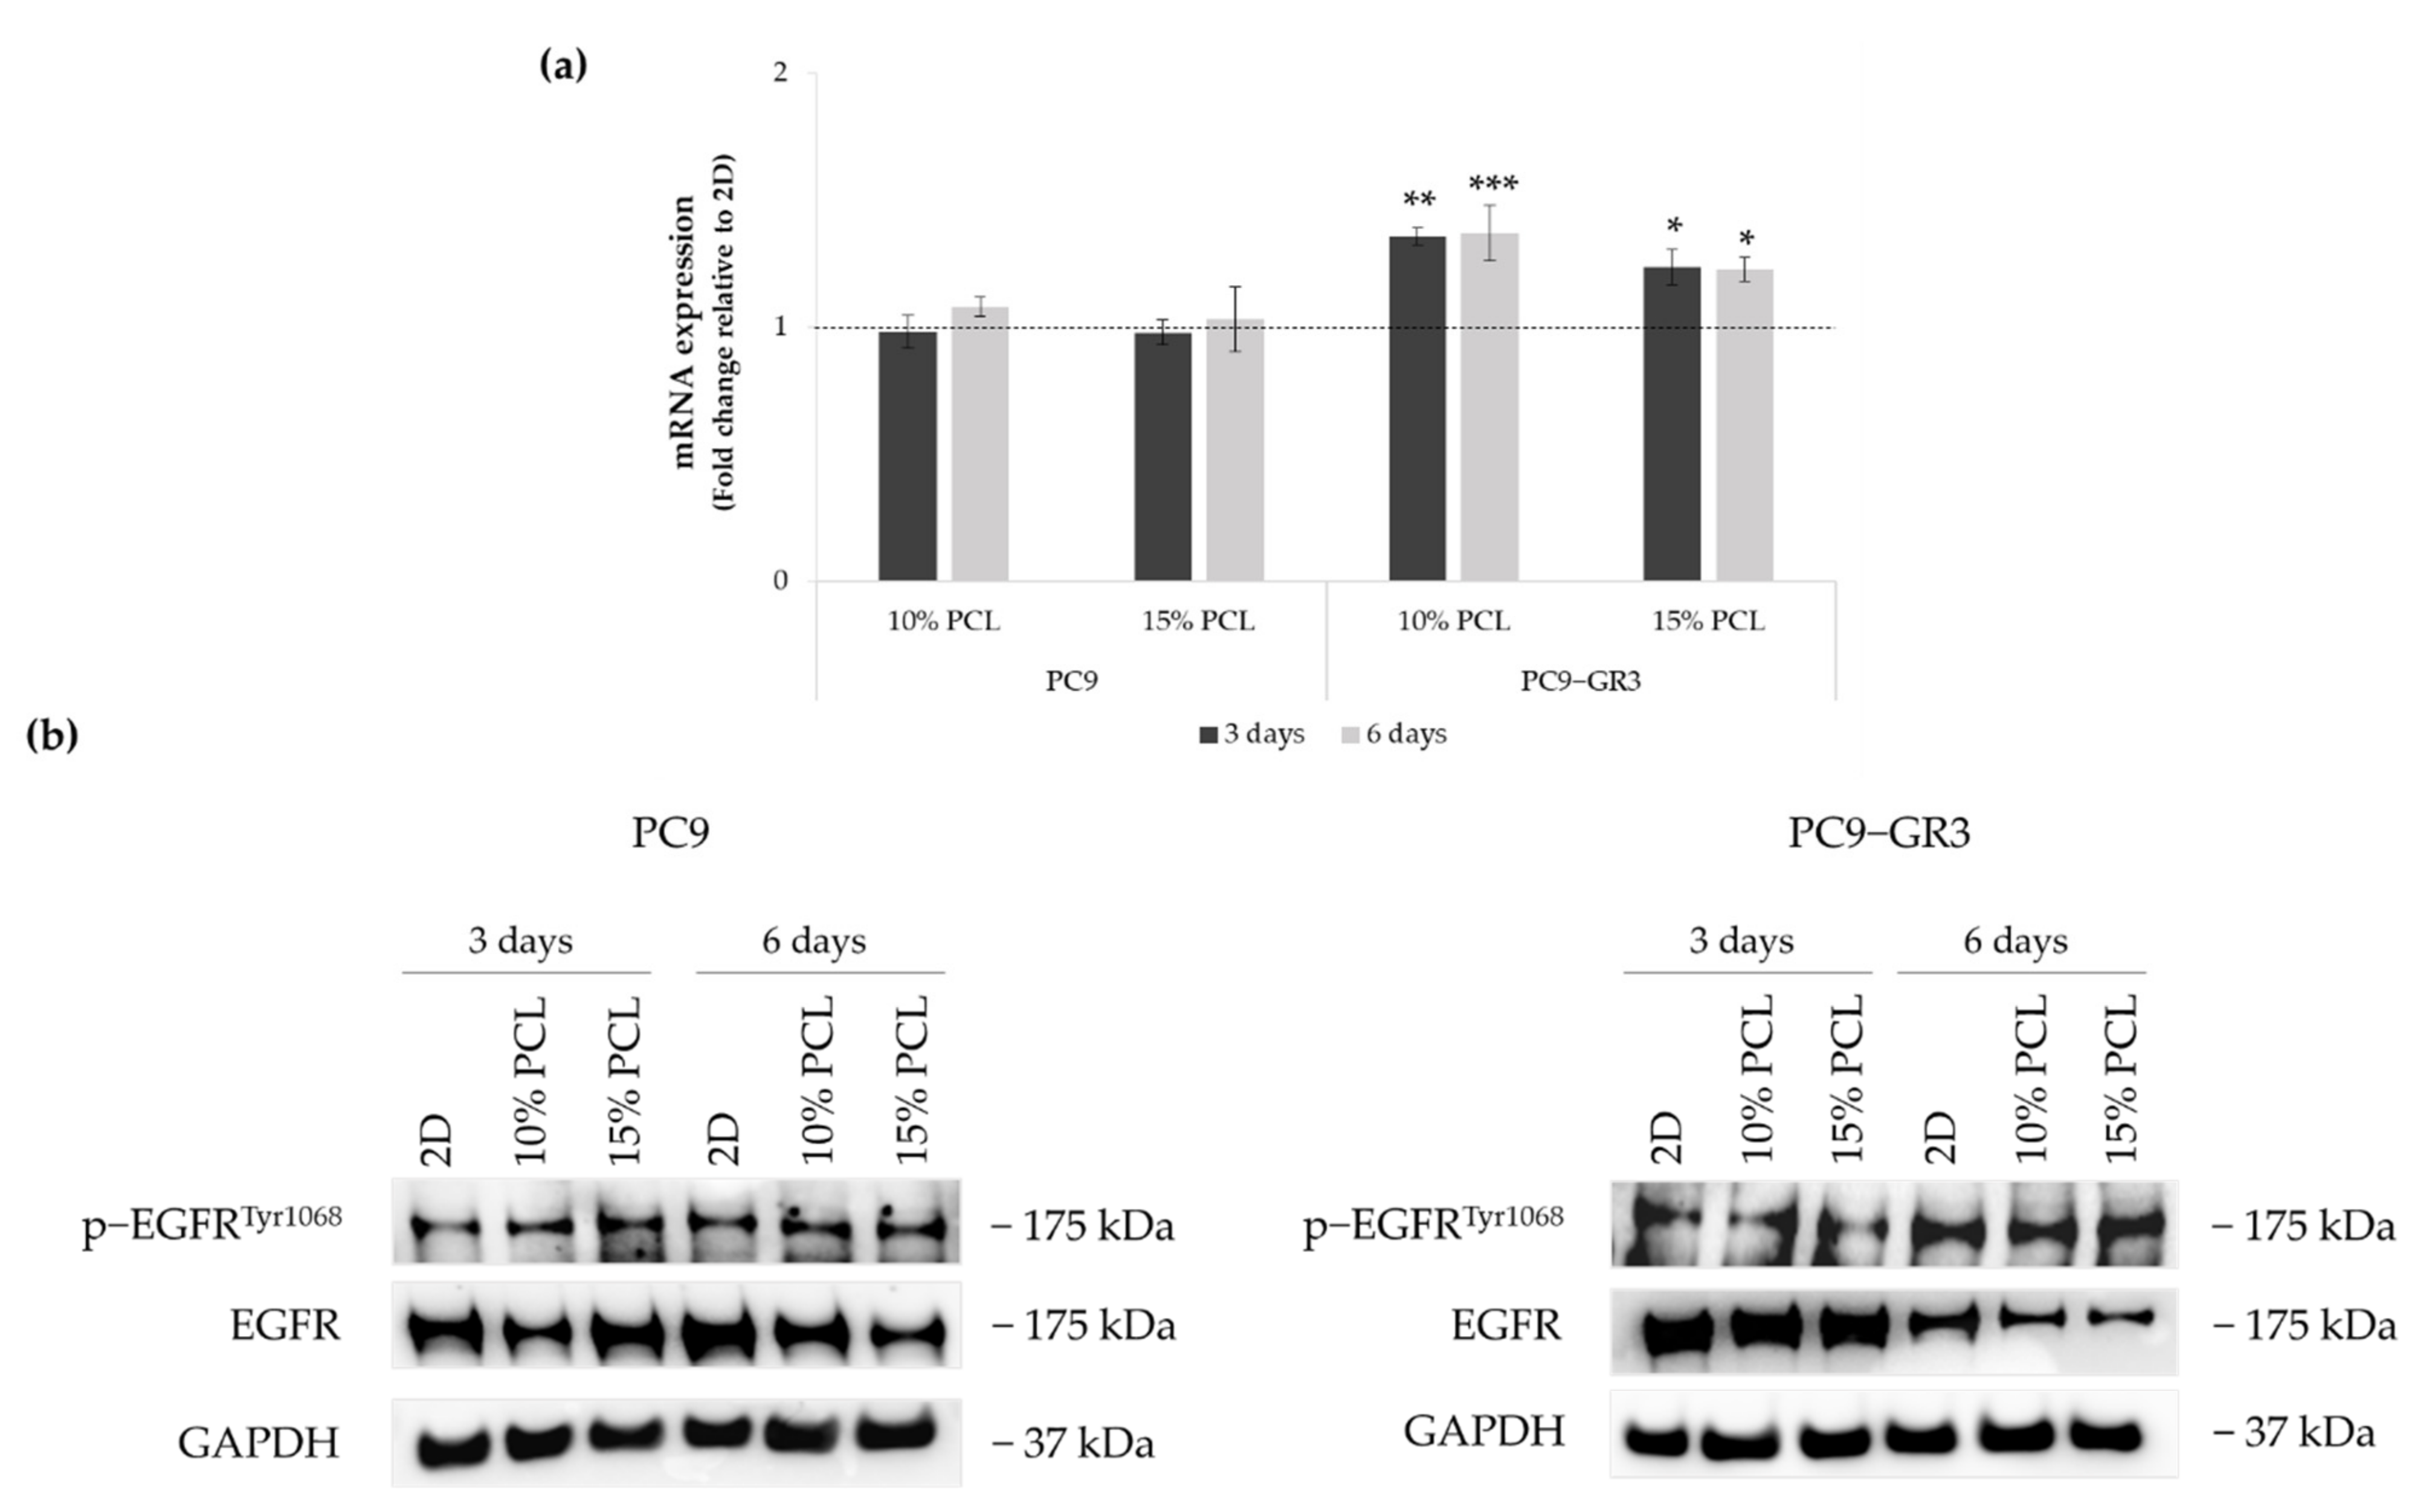

3.4. Evaluation of EGFR Status in Sensitive and Resistant EGFRm Lung Adenocarcinoma Cell Models Cultured on PCL-ES Scaffolds